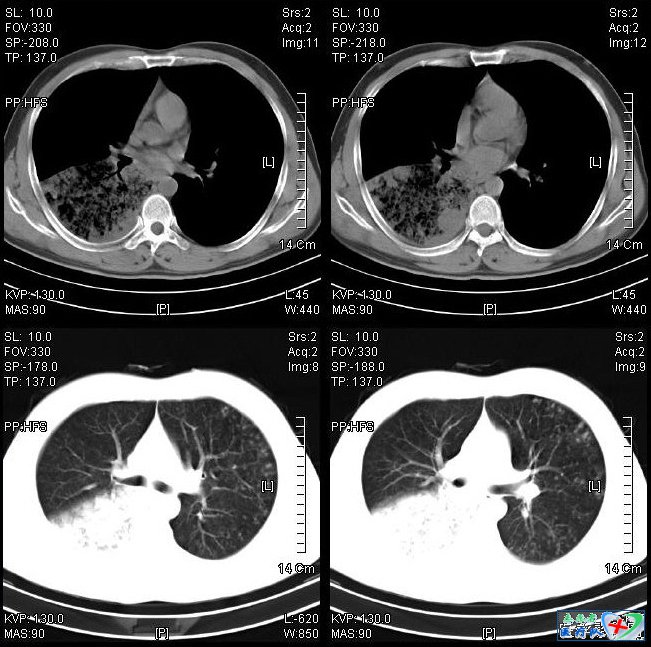

9、黑边征(黑胸膜线):

由于胸壁和肺内微石的衬托,再肺实质和肋骨之间出现细条状低密度影。黑边征是肺泡微石症的X线征象,HRCT已经证实,在X线看到的黑边征,其实是胸膜下微小囊肿沿胸膜面排列而成的。肺泡微石症因为重力的作用,病变分布主要在中下肺野。在X线上的过度曝光状态可以检出更多的钙化结节。病灶形态多样,包括磨玻璃状、条纹状沿支气管分布,同时可见纤维索条影、支气管血管束不规则及囊肿形成。这种复杂的表现反映了肺泡微石症反复的过程,可形成克氏B线,也可形成黑边征。